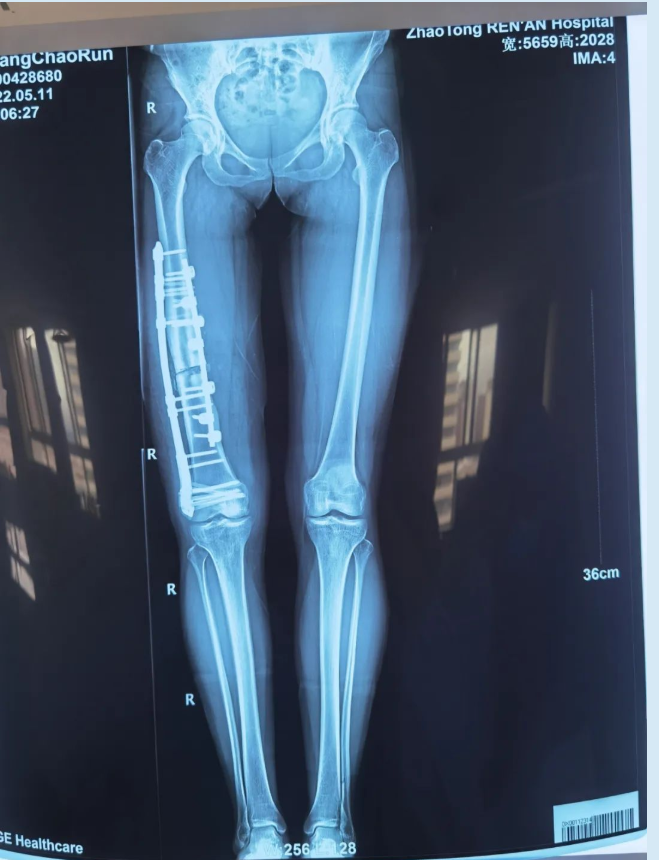

术后患者右下肢畸形完全矫正,双下肢等长,再经术后康复治疗,右膝关节活动自如,终实现多年正常步态、自信满满“潇洒走一回”的夙愿。

(术后影像)